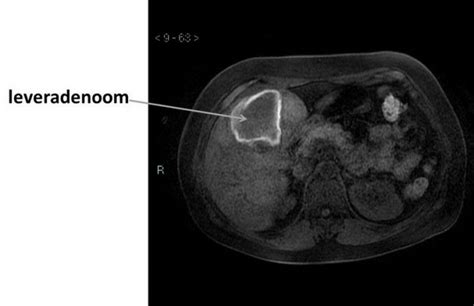

Wat is een Leveradenoom?

Een leveradenoom is een goedaardige tumor van de lever. Dit betekent dat het een niet-kwaadaardige afwijking is, in tegenstelling tot levertumoren die wel kanker bevatten. Leveradenomen komen vooral voor bij vrouwen in de vruchtbare leeftijd, tussen 20 en 50 jaar, hoewel ze ook bij mannen kunnen voorkomen. Het is een zeldzame aandoening, waarbij ongeveer zes op de honderdduizend mensen zo'n tumor ontwikkelt.

Leveradenomen zijn meestal duidelijk begrensd en afgekapseld, wat hen onderscheidt van kwaadaardige levertumoren. De grootte van een leveradenoom kan sterk variëren, van 1 centimeter tot meer dan 20 centimeter.

- CT-scan: Dit onderzoek maakt gebruik van röntgenstralen om nauwkeurige beelden van de lever te verkrijgen.